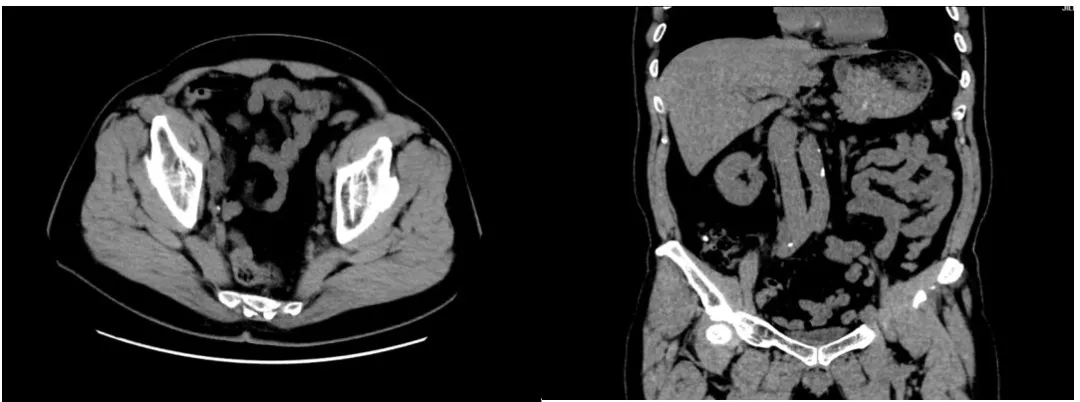

胸部CT、腹部及盆腔CT(2025-02-06)

淋巴结转移

肺部多发转移灶,盆腔多发淋巴结转移。

膀胱后壁不均匀增厚,肿瘤性病变与前列腺外压待鉴别;右侧输尿管中下段显示不清,建议泌尿系CT增强检查,膀胱少许积气及积血,建议复查,腹主动脉及双侧髂动脉旁多发肿大淋巴结,考虑转移,前列腺增生及双侧精囊腺改变。

前列腺磁共振(2025-02-06)

前列腺体积增大,其内信号于T2-FS不均匀增高,DWI可见高信号;中央带增大为主,双侧外周带受压变扁,增强后前列腺可见明显不均匀强化。双侧盆壁见多发大小不等的结节影及肿块影,较大者最大截面约72mm×55mm。考虑前列腺癌,侵及膀胱,盆腔淋巴结转移、骨转移。